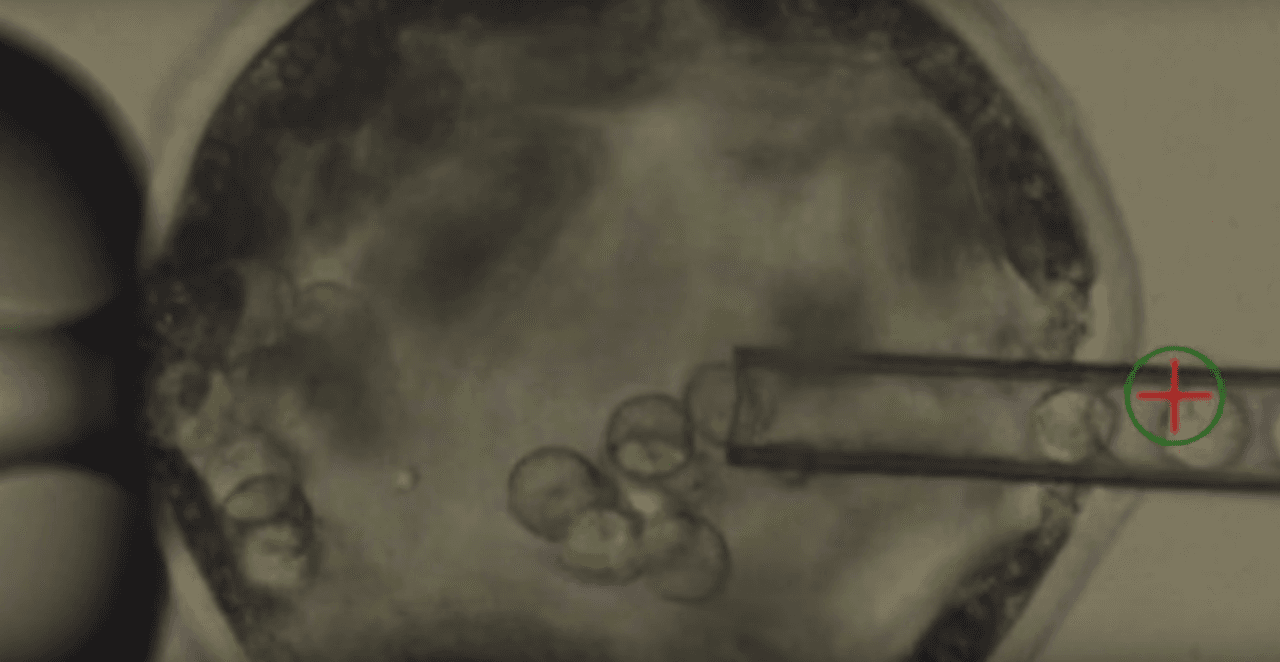

El primer método es introducir los órganos de un animal en otro animal, con cierto riesgo frente a la respuesta del sistema inmune que pueden generar el rechazo de los órganos. El segundo método, es comenzar la hibridación en el embrión, es decir introducir las células de un animal en el embrión de otro animal, así comienzan a desarrollarse en conjunto formando un organismo híbrido.

Cuando los embriones sobrevivieron fueron implantados en cerdos adultos, donde se desarrollaron por 3 o 4 semanas para ser luego removidos y analizados. Así, siguiendo esta técnica, se desarrollaron 186 embriones quiméricos, con 100 000 células humanas cada uno, aproximadamente.